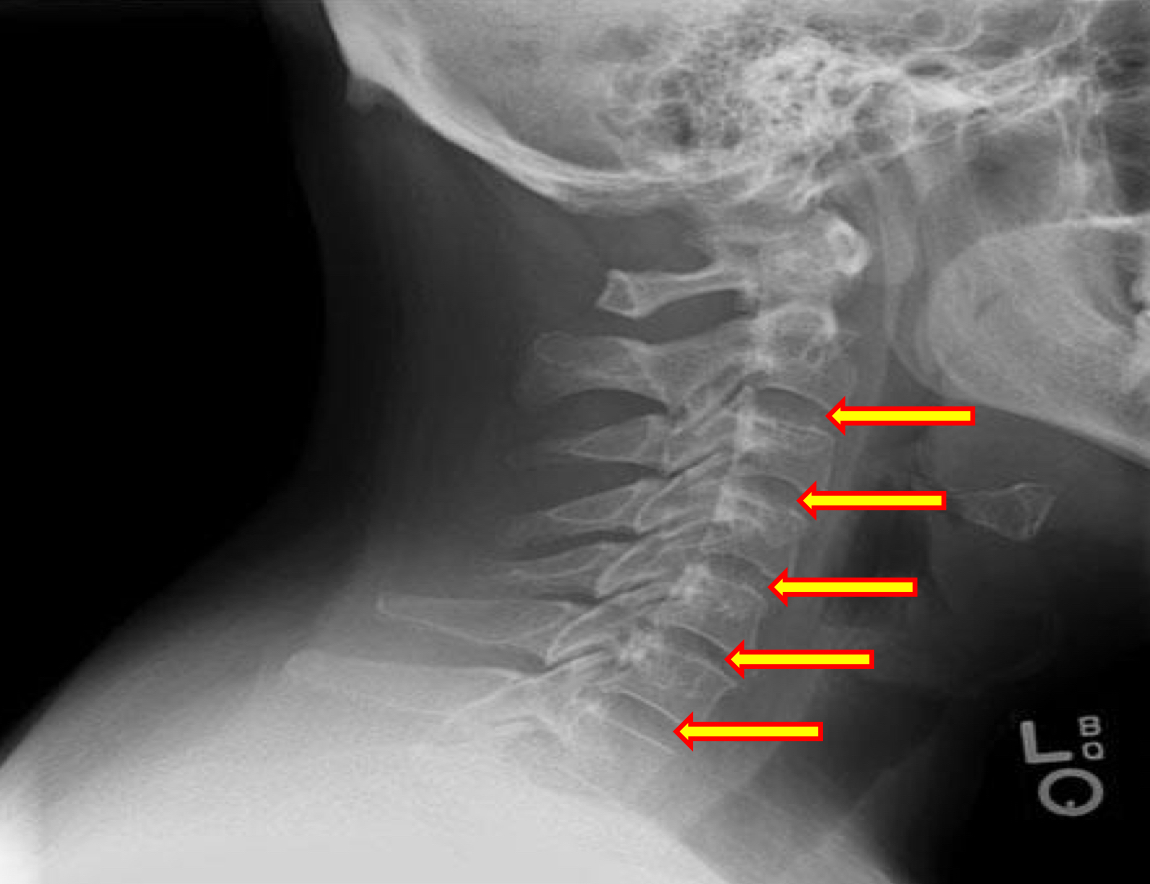

What view is this?

Lateral Cervical

What is this?

Vertebral Bodies

What is this?

Superior and Inferior Endplate Tips

What is this?

Disc space

What is this?

Junction of Lamina/tip of Spinous

What is this?

Uncinate Processes

What is this?

Inferior Aspect of Vertebral Bodies